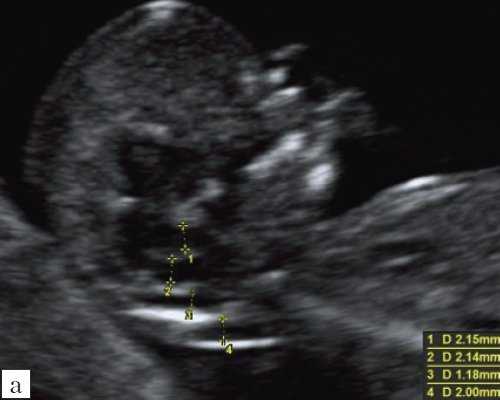

Особенностями визуализации этих структур является их гипо/анэхогенность. Так, при сроках 11-14 недель беременности таламус, ствол мозга, средний мозг выглядят практически анэхогенными. Итак, нормальная ультразвуковая анатомия этих структур головного мозга плода имеет следующие особенности: ствол и IV желудочек выглядят как анэхогенные продолговатые структуры, имеющие непосредственную близость (как бы выходящие) из диэнцефалона и среднего мозга. Все выше перечисленные анатомические структуры могут быть измерены и должно быть оценено их взаиморасположение (рис. 2, а).

а) На эхограмме:

1 - ствол мозга;

2 - интракраниальное пространство, или IV желудочек;

3 - большая цистерна головного мозга;

4 - воротниковое пространство.

б) Вид "осьминожки":

- красный цвет - диэнцефалон (таламус), со стволом мозга (верхняя ножка) и IV желудочком (нижняя ножка);

- желтый цвет - большая цистерна головного мозга;

- синий цвет - воротниковое пространство.

Новый ультразвуковой маркер в изучении нормальной ультразвуковой анатомии головного мозга плода в срок 11-14 недель беременности

Особенности визуализации изложенных выше структур в данном сроке позволили нам выделить и назвать новый ультразвуковой маркер нормальной ультразвуковой анатомии мозга плода. Структуры головного мозга плода в этой области схожи с осьминогом, у которого есть голова и две приблизительно равновеликие по диаметру ножки, представляющие собой ствол мозга и IV желудочек. Ниже ножек "осьминожки" визуализируется 2 "подушки осьминожки" - это два анэхогенных пространства - большая цистерна и воротниковое пространство (рис. 2, б).

Так как речь идет о сроках первого скрининга, т.е. раннего осмотра, новый ультразвуковой маркер мы назвали "осьминожкой" (рис. 3).

а) Стрелками указана голова "осьминожки" - диэнцефалон (таламус).

б) Красный цвет - диэнцефалон (таламус), со стволом мозга (верхняя ножка) и IV желудочком (нижняя ножка); желтый цвет - большая цистерна головного мозга; синий цвет - воротниковое пространство.

Как сказано выше, имеет значение и измерение ножек "осьминожки", так среднее значение диаметра нижней ножки, т.е. IV желудочка в зависимости от КТР в срок 11-14 недель варьирует от 1,5 до 2,5 мм (рис. 4).

Рис. 4. Измерение и взаимоотношение ножек "осьминожки" - ствола мозга и IV желудочка у плода, беременность 12 недель.

Измерение ножек "осьминожки".

Красный цвет - диэнцефалон (таламус), со стволом мозга (верхняя ножка) и IV желудочком (нижняя ножка); желтый цвет - большая цистерна головного мозга; синий цвет - воротниковое пространство.